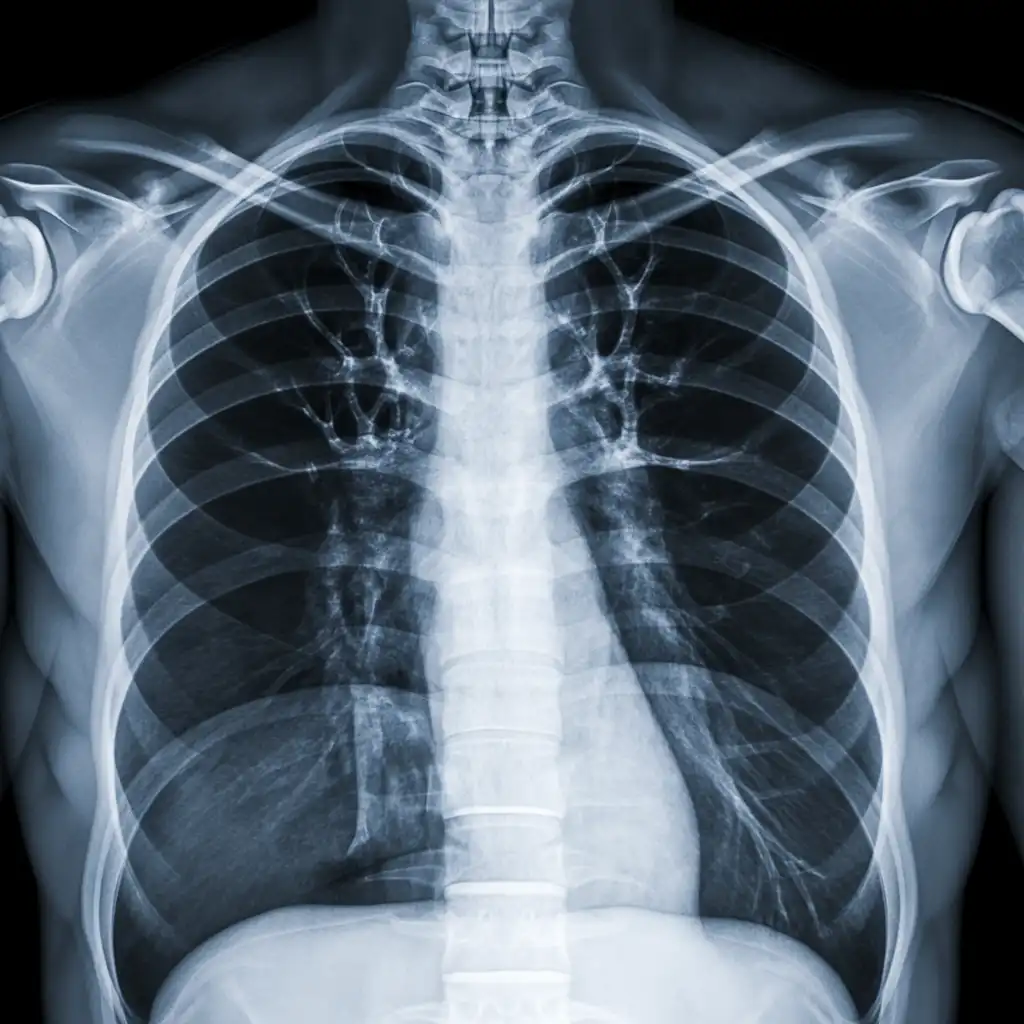

Una lastra a domicilio è una radiografia eseguita direttamente a casa del paziente, grazie all’intervento di un tecnico sanitario qualificato dotato di apparecchiatura digitale portatile.

L’esame viene effettuato sul posto, senza necessità di spostare la persona dal letto o dalla poltrona, e garantisce una qualità diagnostica paragonabile a quella di un reparto ospedaliero.

Una volta acquisite, le immagini vengono trasmesse al medico radiologo, che le analizza e redige il referto in tempi brevi.

Nel corso degli anni abbiamo effettuato migliaia di radiografie a domicilio in abitazioni private, RSA, centri di assistenza e strutture per anziani, utilizzando apparecchi digitali portatili certificati che garantiscono immagini precise e tempi di esecuzione rapidi.